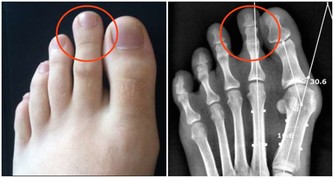

不曉得大家有沒有指甲就會不小心嵌入肉裡的經驗?

以前小時候不太會剪腳趾甲,就很容易會變成這種狀況,

指甲嵌進去肉裡之後就會開始發腫、發炎,甚至還會化膿!

這樣就可能導致細菌進入傷口,甚至造成嚴重的感染!